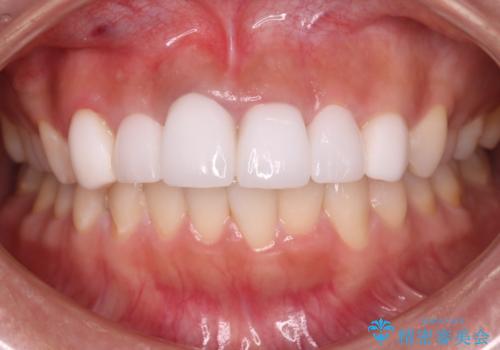

- 他院で治療した前歯の色が気になるということで来院された患者様です。前歯に色の差があり、レントゲンから内部にう蝕も見られたため、審美性に優れ、う蝕になりにくいオールセラミッククラウンで治療いたしました。

清掃性も上がったおかげで、歯肉の状態も良好に保てています。

色の調和もとれたので非常に満足いただけました。